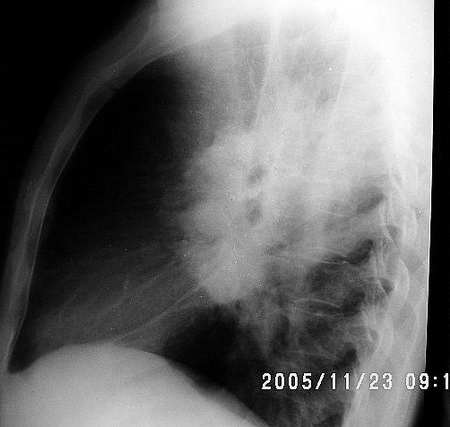

男 40 胸闷 咳嗽半年 物理检查无阳性发现

临床资料:男,40岁,胸闷,咳嗽半年,余无异常

影像表现:双侧肺门对称性增大,双肺野内纹理增强

诊断:结节病

病史:男 40 胸闷 咳嗽半年

征象:右肺门明显肿大,右上纵膈增宽并见软组织影,左肺门增大不明显或略大。

考虑:结节病,中青年多见,常侵犯肺、双侧肺门淋巴结,纤维支气管镜检查活检。此外,血清免疫球蛋白增高、高血钙症、高尿钙症、碱性磷酸酶增高等对诊断有一定的意义。

结果 结节病 病人提供外院ct片经激素治疗好转